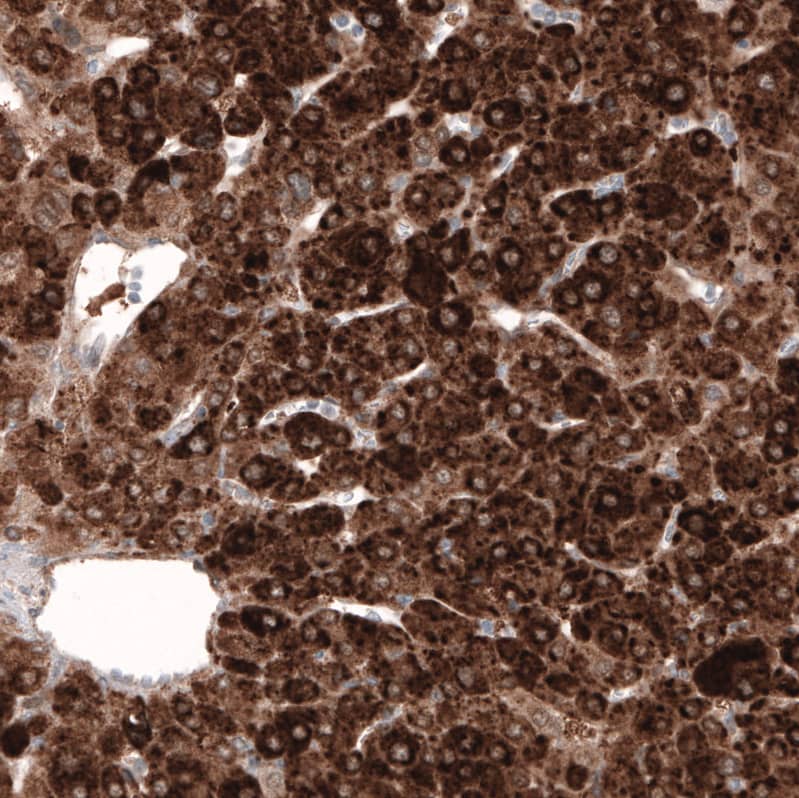

Staining of human liver cancer shows strong cytoplasmic positivity in tumor cells.